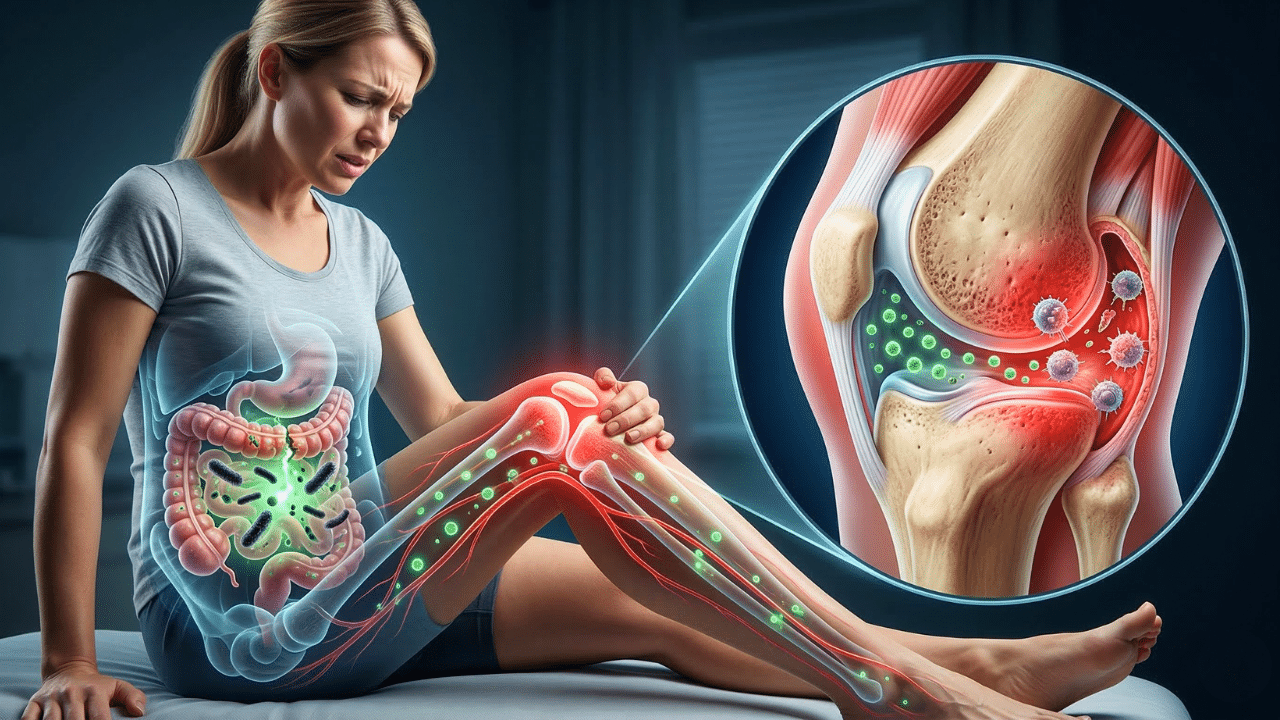

Imagine the lining of your intestines like a tightly woven mesh. Their job is to allow nutrients to pass into the bloodstream while keeping harmful substances — such as undigested food particles, bacteria, and toxins — out. In a healthy gut, this works perfectly. But when you have Leaky gutthe connections in that network become loose. This is called intestinal hyperpermeability.

When the gut microbiome is out of balance (a condition called dysbiosis), some harmful bacteria can multiply. These bacteria produce toxins called lipopolysaccharides (LPS). This LPS is particularly bad because it can break down the glue that holds intestinal cells together. This creates gaps, allowing LPS and other bacteria to leak directly into the bloodstream. Your body’s first line of defense has been compromised.

3. The toxic journey: from your gut to your joints

Once these bacterial toxins reach the blood, the liver, the body’s main detoxification organ, attempts to filter them out. But our modern, highly processed, high-carb diet puts the liver under constant stress. It gets exhausting. When the liver can’t keep up, these toxins spread freely throughout the body, leading to a chronic, low-grade inflammatory condition called metabolic endotoxemia.

Here’s the important part for your knees: These LPS toxins have a special affinity for the synovial capsule, the tissue that lines and lubricates the knee joint. They accumulate there, and your immune system, sensing the presence of a foreign invader, launches an attack. The problem is that it cannot distinguish between the poison and your tissue. It begins by attacking the synovial capsule itself. This is an autoimmune process. Your body causes inflammation, redness, and pain in your knee. We call it “wear and tear”.